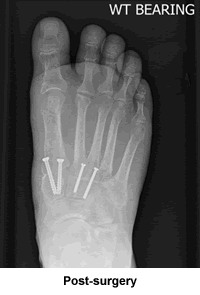

My right foot has been particularly problematic since I was six years old. It took two bunionectomies before that particular issue was finally resolved, and all was tolerably well until a year ago. The right foot once again reared its ugly (and I do mean ugly) head and began giving me all kinds of pain and discomfort. The orthopedic surgeon who had performed my second bunionectomy ordered a set of radiographs. When he saw what was happening he sent me to New England Baptist to see Dr. Leavitt. Dr. Leavitt was very impressed (from a medical science standpoint) and sympathetic (from a humanistic standpoint) as we looked at the x-rays and discussed what was happening to the bones. While not downplaying the inconvenience that I would go through, he confidently explained what he would be doing in surgery and how he had no doubt the problems would be resolved to my satisfaction. He came to see me right before and after the surgery, kind, upbeat, and optimistic. This was very reassuring, both to my husband and me.

Once I had the cast off I was amazed at how straight my toes (which had been wandering all over the place) were. I can now use my big toe for a ruler if I have to! Ten weeks later and the scars are fading, the discomfort is negligible, and the swelling is almost gone. Even though at the time of this writing I am still going through physical therapy, there is no doubt in my mind that it has all been worth it.